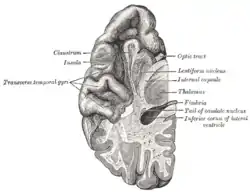

![]() Вінцевий розтин навпроти мосту. Острівцева частка згори праворуч | |

Вінцевий розтин мозку через третій шлуночок.